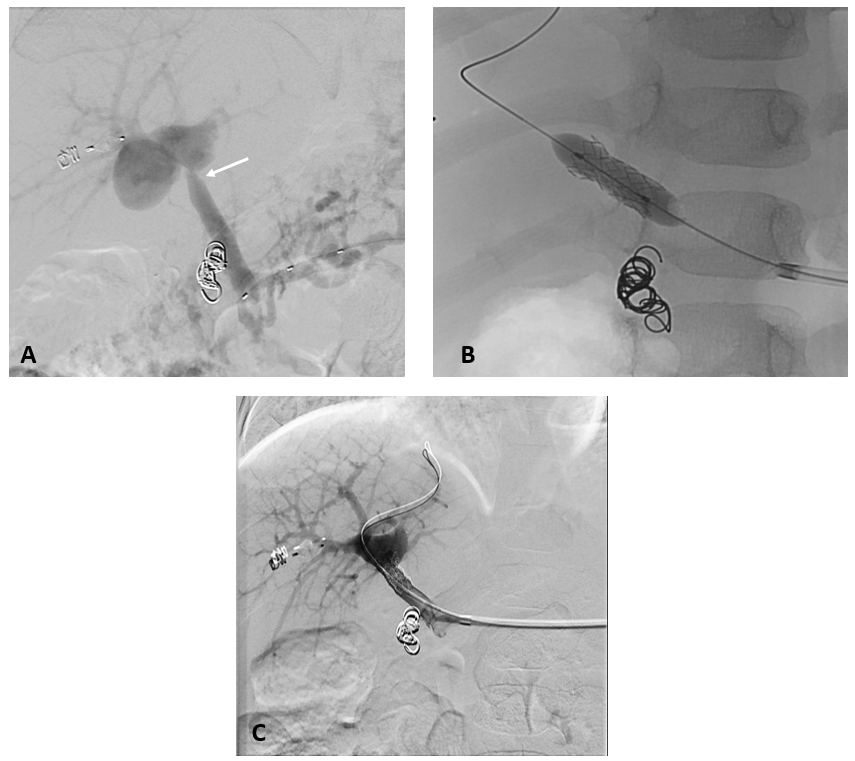

7 jähriger Junge mit Kurzdarmsyndrom und Leberzirrhose

Als Folgen des Pfortaderhochdrucks war die Milz vergrößert (Splenomegalie) und es traten Krampfadern der Speiseröhre (Ösophagusvarizen) auf. Um den Hochdruck zu entlasten wurde ein TIPS angelegt. Dazu wird aus der rechten Lebervene (A) mit einer speziellen Nadel ein Pfortaderast punktiert (B). Anschließend wird die Pfortader mit einem Draht sondiert (C) und die geschaffene Verbindung mit einem Ballon aufgedehnt und anschließend mittels Gefäßstütze (Stent) geschient (D). Durch diese künstliche Verbindung kann das Pfortadersytem deutlich druckentlastet werden.